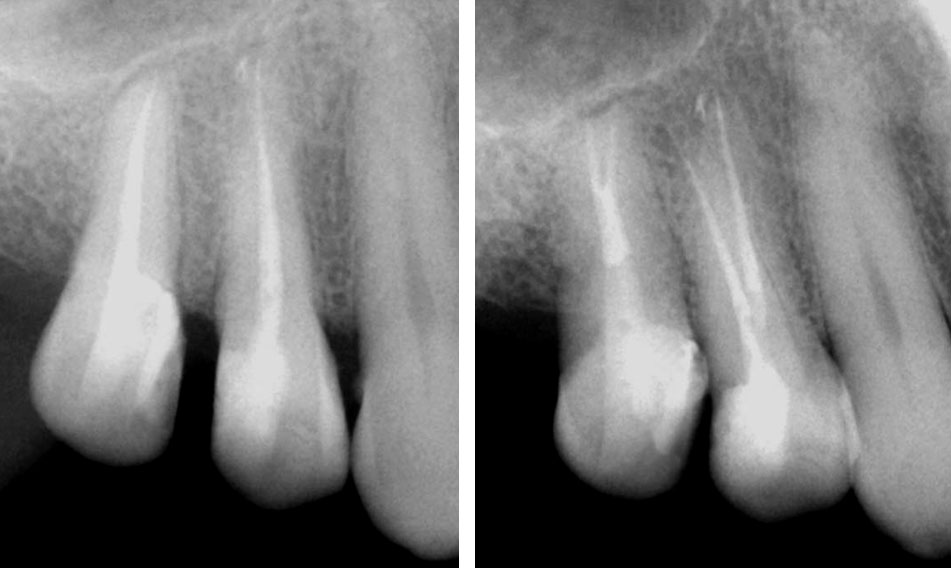

Central incisor referred after previous clinician had accessed the tooth and was unable to locate the calcified canal.

Removal of temporary restoration shows palatal perforation (red arrow) and a calcified canal in the middle (yellow arrow)

Palatal perforation was supra-crestal and was repaired with GIC

Calcified canal located

Calcium hydroxide placed

Recall after 10 days. Sinus tract healed

Post-op & 1 year recall